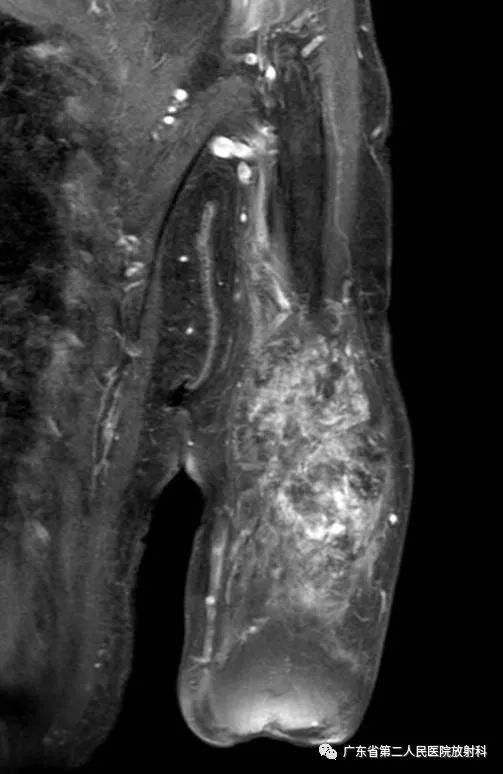

左上肢前壁截肢术后观,左上臂中下段见团块状异常信号,病灶信号明显不均,整体以长T1长T2信号影为主,增强扫描呈明显不均匀强化,末端球形膨大,内见散在少许团絮状短T2长T1且无强化信号。冠状位示病灶整体呈梭形改变,边界欠清,部分包绕肱骨下段,以长T1长T2信号为主,散在少许短T2信号,增强扫描明显不均匀强化,内见散在少许团絮状短T2长T1且无强化信号。肱骨下端边缘欠光整,骨髓未见明确异常信号。